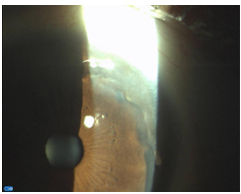

Ojo derecho: Adelgazamiento corneal periférico, desde h-11 a h-3, avascular, con línea central más profunda y córnea transparente entre limbo esclero-corneal y lesión. (

Figura 1 y figura 2 )

Figura 1 .Biomicroscopía anterior a iluminación difusa de la córnea.

Figura 2. Biomicroscopía anterior a iluminación focal en hendidura de la córnea.

En el primer caso, se trata de esta degeneración en su forma de presentación "surco marginal", que se forma por adelgazamiento de la córnea periférica a expensas de las capas superficiales, con una concavidad del borde central más abrupto que en periferia. Se sitúa entre el limbo y la banda de opacidad, con una anchura típica de 1-2 mm.

A medida que se adelgaza el tejido se hace más transparente y la opacidad queda reducida a una línea festoneada en el borde central del surco o puede fragmentarse en una serie de manchas. Los vasos, radiales y paralelos, pero con anastomosis, no sobrepasan esta línea. En todo momento se mantiene la integridad del epitelio corneal. Inicialmente localizado y generalmente superior, el surco puede progresar en forma de anillo 360° en la córnea.5, 6